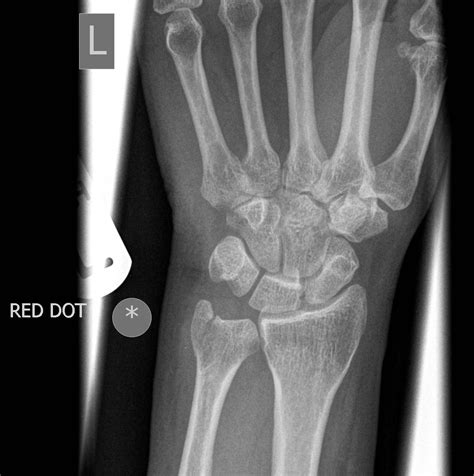

Interpreting a Normal Wrist Xray

Interpreting a Normal Wrist Xray requires a trained eye. Radiologists look for several key features:

• Bone density and structure

• Alignment of the bones

• Presence of fractures or dislocations

• Signs of arthritis or other joint disorders

• Soft tissue abnormalities

Here is a table outlining common findings in a Normal Wrist Xray:

Finding Description

Normal Bone Density Bones appear uniform and dense without any signs of thinning or erosion.

Fracture Visible break or crack in the bone, often accompanied by misalignment.

Dislocation Bones are out of their normal position, often due to trauma.

Arthritis Joint space narrowing, bone spurs, and other signs of wear and tear.

Soft Tissue Swelling Increased density around the joints, indicating inflammation or injury.